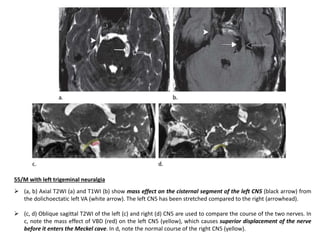

55/M with left trigeminal neuralgia

 (a, b) Axial T2WI (a) and T1WI (b) show mass effect on the cisternal segment of the left CN5 (black arrow) from

the dolichoectatic left VA (white arrow). The left CN5 has been stretched compared to the right (arrowhead).

 (c, d) Oblique sagittal T2WI of the left (c) and right (d) CN5 are used to compare the course of the two nerves. In

c, note the mass effect of VBD (red) on the left CN5 (yellow), which causes superior displacement of the nerve

before it enters the Meckel cave. In d, note the normal course of the right CN5 (yellow).